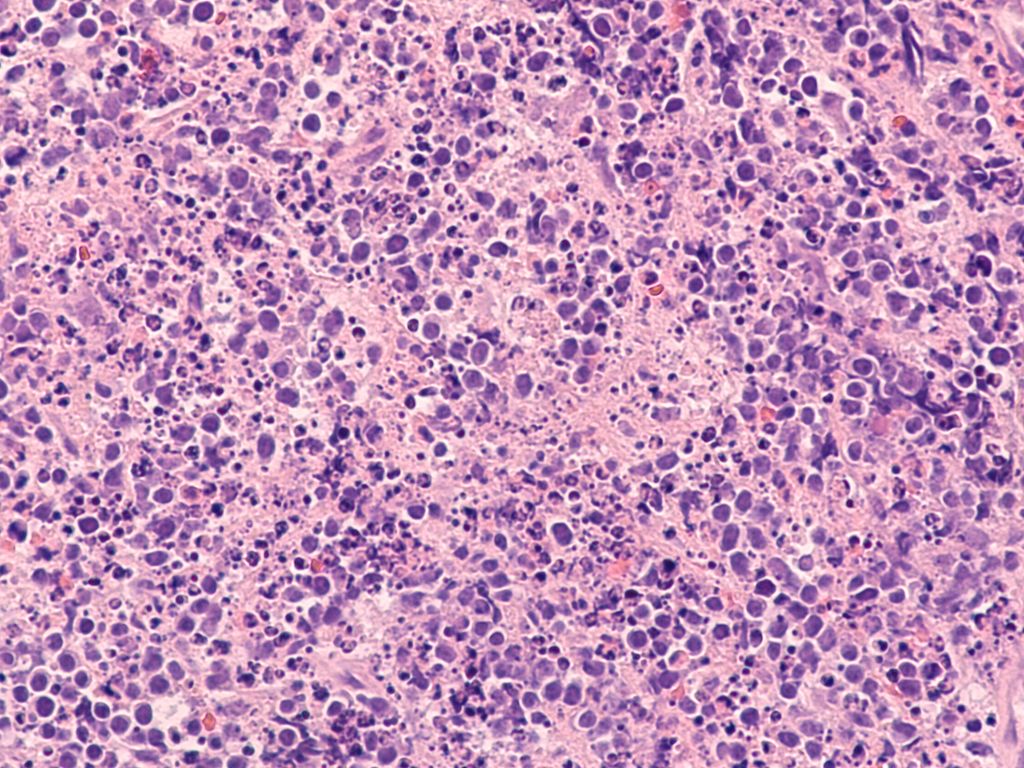

„Das geht unter die Haut!“– Hautläsion mit hämatologischer Ursache?

Onkologie | Dermatologie | Hämatologie | Pathologie

| gültig bis Januar 2027

Onkologie | Dermatologie | Hämatologie | Pathologie